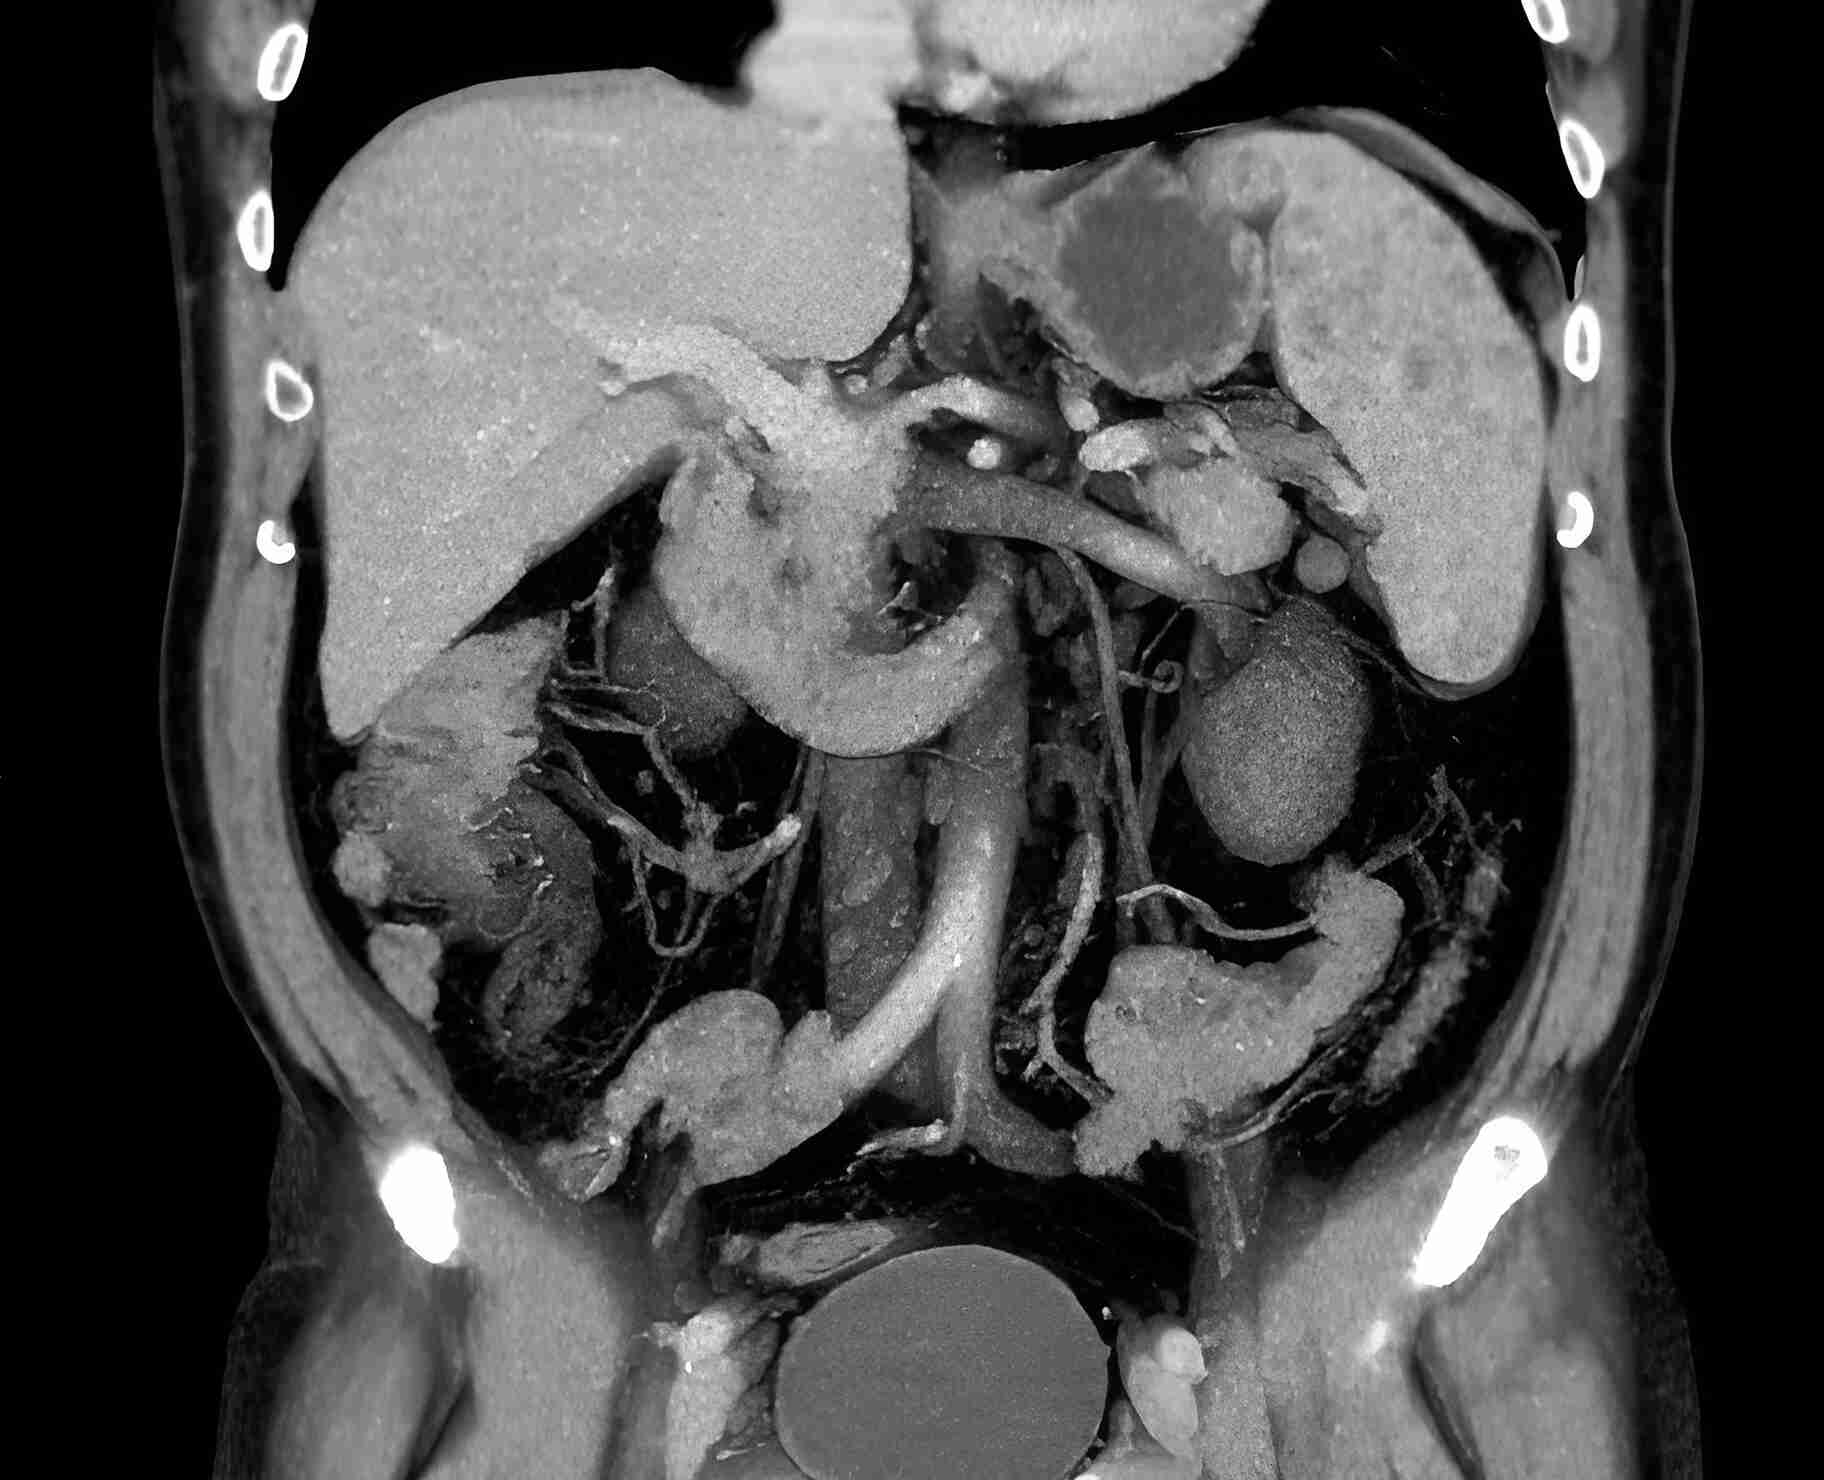

КТ диагностика тубоовариального абсцесса: Подходы и изображения

Раздел: Объективный взгляд